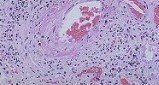

組織活檢是PAN最有力的診斷手段,發現有中小動脈的壞死性血管炎,並與多系統的臨床表現相吻合時可確診。在有症狀的部位如皮膚、睪丸、附睪骨骼肌和周圍神經的活檢最具有價值但對無病變部位的活檢一般難以確診。